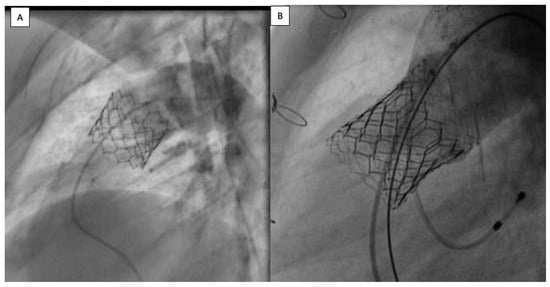

3.3. Procedures